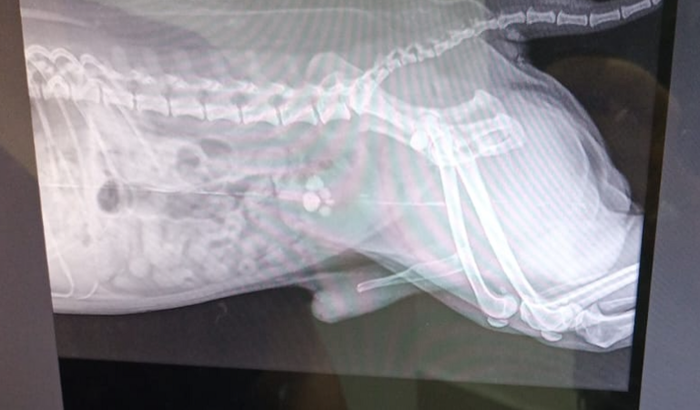

Ajudem na cirurgia do Joaquim

O Joaquim eSta com 6 perrado na bexigência, semana qué vem tem qué fazer a cirurgia anesse qué se agrave. No momento estou sem condições de custiar a cirurgia na clínica ve terminaria. ver tudo

O Joaquim eSta com 6 perrado na bexigência, semana qué vem tem qué fazer a cirurgia anesse qué se agrave. No momento estou sem condições de custiar a cirurgia na clínica ve terminaria.